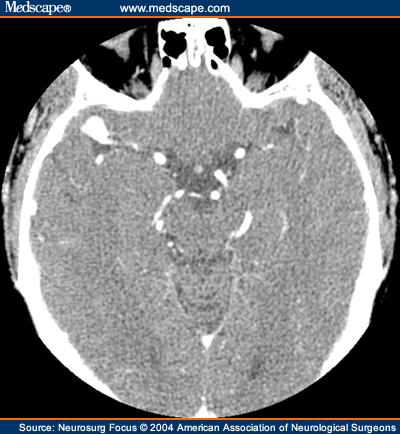

Traditionally, brain aneurysms were treated with open brain surgery. Ongoing monitoring can reduce this risk and guide a. Most brain aneurysms occur at the base of the brain.

A brain or cerebral aneurysm is a cerebrovascular disorder that is caused when the wall of an artery in the brain becomes weak and balloons outward.

Natural history, clinical outcome, and risks of surgical and endovascular. Small, unchanging aneurysms usually don't have any signs or symptoms. The goals of treatment once an aneurysm has ruptured are to prevent further bleeding and potential permanent brain damage. People who have unruptured aneurysms should talk to a doctor about how to minimize the risk of rupture.